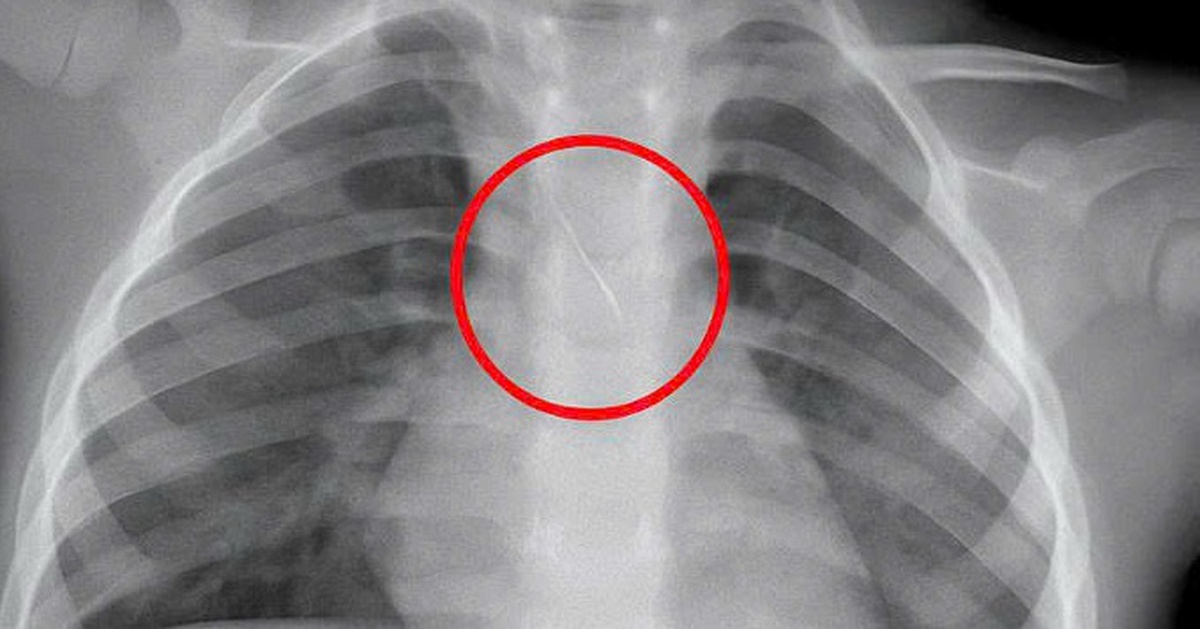

Kim chọc tủy dài 22mm rơi vào đường thở bé trai 3 tuổi khi làm răng

Bé trai nhập viện trong tình trạng ho sặc dữ dội, được xác định hóc kim chọc tủy dài 22mm rơi vào đường thở khi đang làm răng.